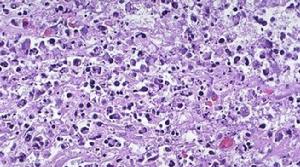

形態學觀察細胞凋亡的變化是多階段的,細胞凋亡往往涉及單個細胞,即便是一小部分細胞也是非同步發生的。首先出現的是細胞體積縮小,連線消失,與周圍的細胞脫離,然後是細胞質密度增加,線粒體膜電位消失,通透性改變,釋放細胞色素C到胞漿,核質濃縮,核膜核仁破碎,DNA降解成為約180bp-200bp片段;胞膜有小泡狀形成,膜內側磷脂醯絲氨酸外翻到膜表面,胞膜結構仍然完整,最終可將凋亡細胞遺骸分割包裹為幾個凋亡小體,無內容物外溢,因此不引起周圍的炎症反應,凋亡小體可迅速被周圍專職或非專職吞噬細胞吞噬。

2. 染色細胞:常用姬姆薩染色、瑞氏染色等。凋亡細胞的染色質濃縮、邊緣化,核膜裂解、染色質分割

成塊狀和凋亡小體等典型的凋亡形態。

結果評判:細胞凋亡過程中細胞核染色質的形態學改變分為三期:Ⅰ期的細胞核呈波紋狀(rippled)或呈折縫樣(creased),部分染色質出現濃縮狀態;Ⅱa期細胞核的染色質高度凝聚、邊緣化;Ⅱb期的細胞核裂解為碎塊,產生凋亡小體。

3.透射電子顯微鏡觀察

結果評判:凋亡細胞體積變小,細胞質濃縮。凋亡Ⅰ期(pro-apoptosis nuclei)的細胞核內染色質高度盤繞,出現許多稱為氣穴現象(cavitations)的空泡結構;Ⅱa期細胞核的染色質高度凝聚、邊緣化;細胞凋亡的晚期,細胞核裂解為碎塊,產生凋亡小體。